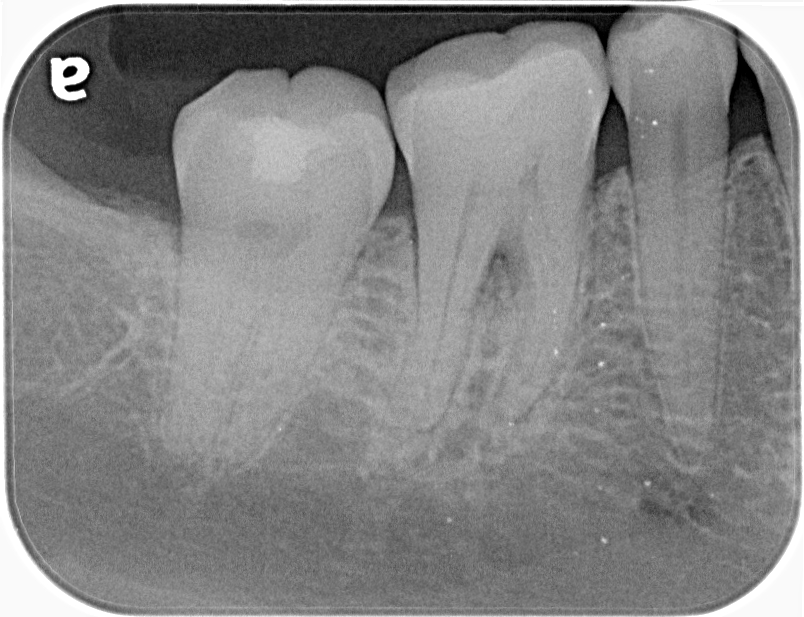

再生療法を行い術後6ヶ月で分岐部のポケット、透過像の改善が認められました。

歯内歯周疾患では根管治療だけではなく、歯周治療の診断と治療を適切に行わなければ改善しません。当院では根管治療のみならず、歯周治療、補綴治療といった総合的な診療を行うことで、歯の保存を積極的におこなっております。